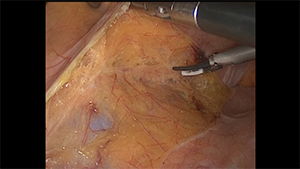

头侧优先的混合入路右半结肠切除术

作者:廖新华 | 作者单位:西安交通大学第一附属医院

发布时间:2020-09-04 14:01:26